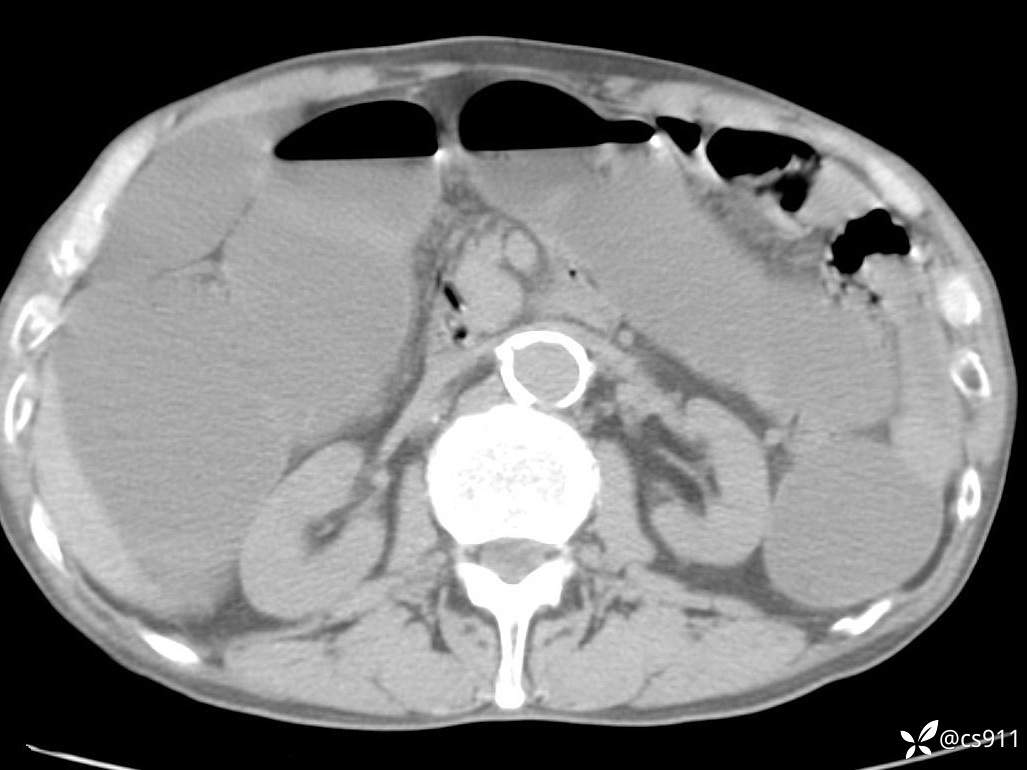

急腹症之急诊CT,原因?答案公布

男,77岁,腹痛、腹胀伴恶心呕吐1天。呕吐胃内容物,非喷射性呕吐,有咖啡色样胃内容物,诉有胃穿孔病史。查体:全腹平,下腹部压痛,全腹无反跳痛,叩诊呈浊音,移动性浊音阴性,肠鸣音减弱,1-2次/分。肛检:直肠未扪及明显肿物,可触及大量粪块。

血淀粉酶(AMY) HH 1859 U/L 35-135